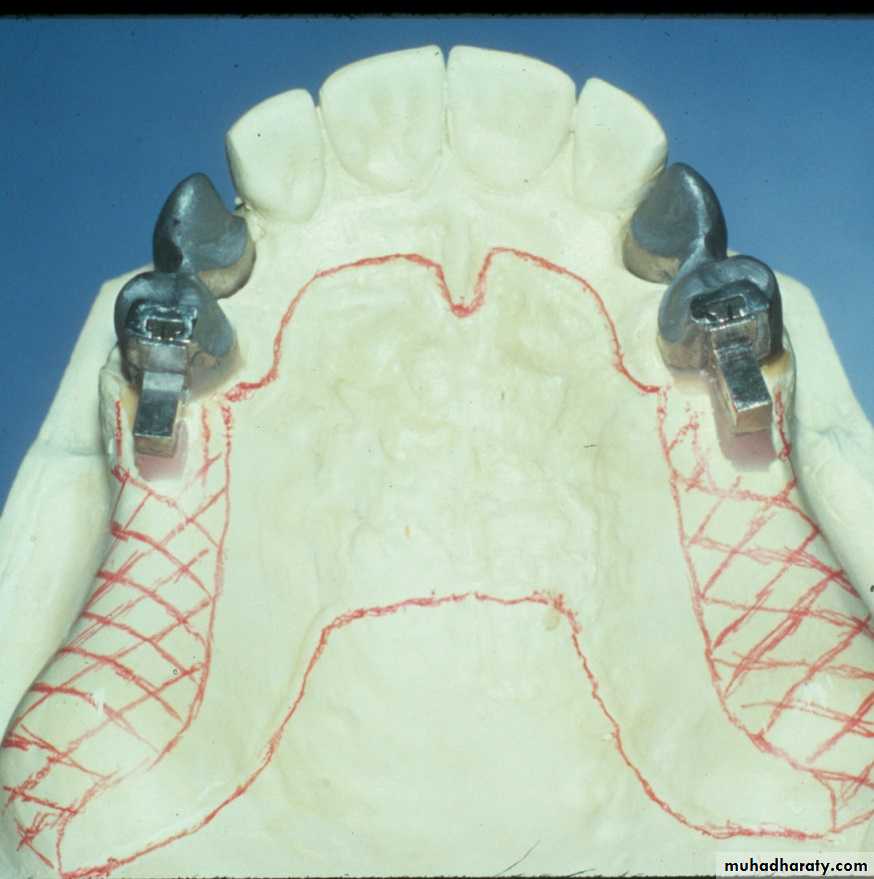

Bar Attachments

►Bar attachments consist of :A bar

Retentive clip(s)Definition of bar attachments

Advantages of Bar Attachments

* Excellent retention & stability for the prosthesis.* The bar acts as an indirect retainer & provides vertical support for the prosthesis preservation of the alveolar bone.

* Rigid splinting & constant mechanism of abutment stabilization

Requirements of Bar Attachments

** Adequate interocclusal

distance**Adequate clearance beneath

the bar

** Adequate Bony support

** Bar should follow ridge